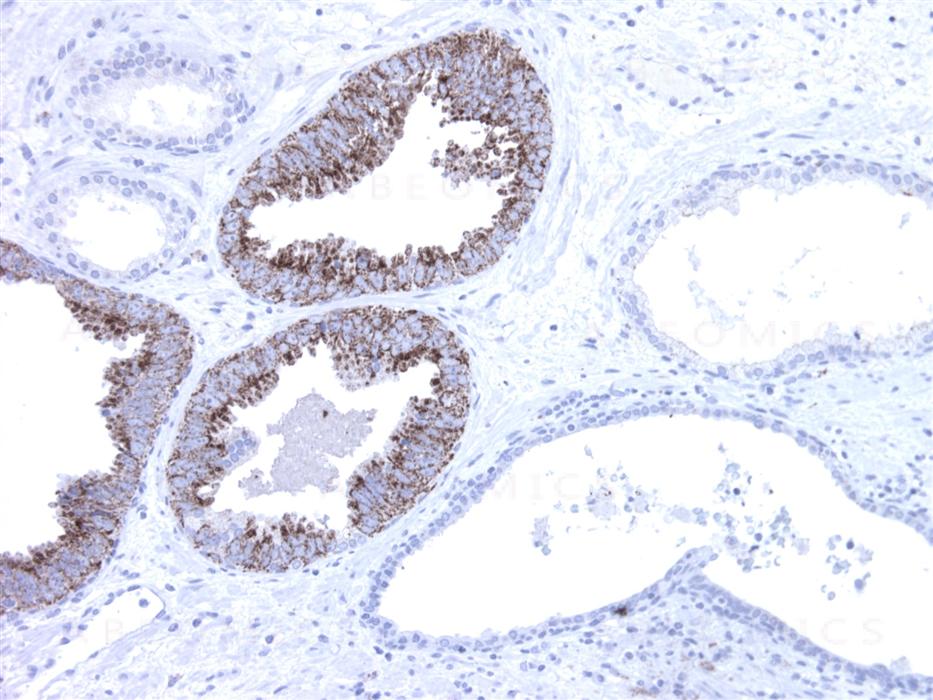

Figure-1: Prostate section has been stained using AMACR antibody (Clone: BS2) with 1:200 dilution. Neoplastic cells have strong granular staining. Note glands without neoplastic cells.

AMACR (alpha-methylacyl-CoA racemase) has been recently described as prostate cancer-specific gene that encodes a protein involved in the beta-oxidation of branched chain fatty acids. Expression of AMACR protein is found in prostatic adenocarcinoma but not in benign prostatic tissue. It stains premalignant lesions of prostate: high-grade prostatic intraepithelial neoplasia (PIN) and atypical adenomatous hyperplasia. AMACR can be used as a positive marker for PIN. Defects in AMACR are the cause of congenital bile acid synthesis defect type 4 (CBAS4); also known as cholestasis, intrahepatic, with defective conversion of trihydroxycoprostanic acid to cholic acid or trihydroxycoprostanic acid in bile. Clinical features include neonatal jaundice, intrahepatic cholestasis, bile duct deficiency and absence of cholic acid from bile.

Immunohistochemical Analysis :-1:200